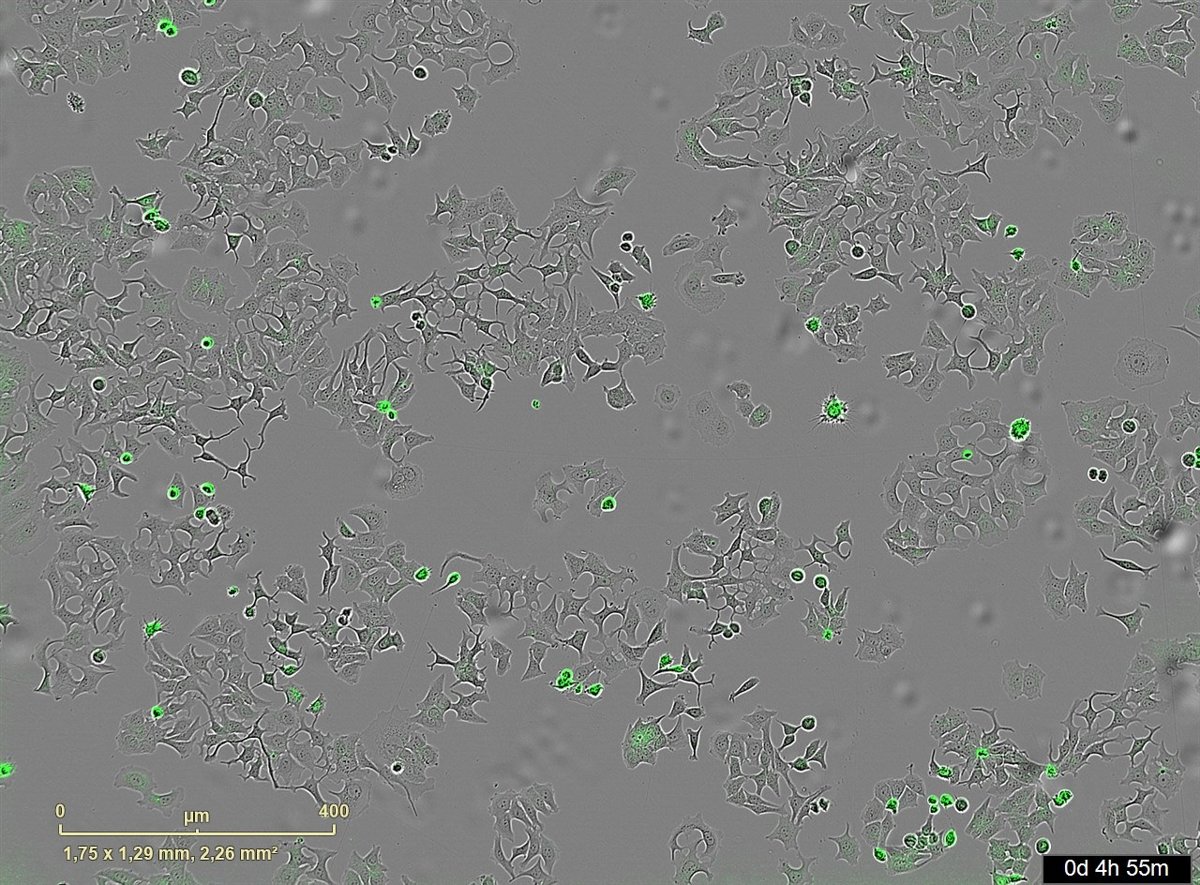

La imagen representa las células de cáncer muertas al activarse su proteína de membrana PAR-1 por la proteasa bacteriana HapA.

La imagen representa las células de cáncer muertas al activarse su proteína de membrana PAR-1 por la proteasa bacteriana HapA. - CIC

Durante el proceso, se han empleado sistemas avanzados de imagen en tiempo real que permiten contar células vivas y muertas, y medir la apoptosis para observar con precisión el bloqueo de las vías. La investigación ha recibido financiación del Consejo de Investigación Sueco, la Sociedad de Cáncer de Suecia, la Unión Europea y la Universidad de Umea (Suecia).